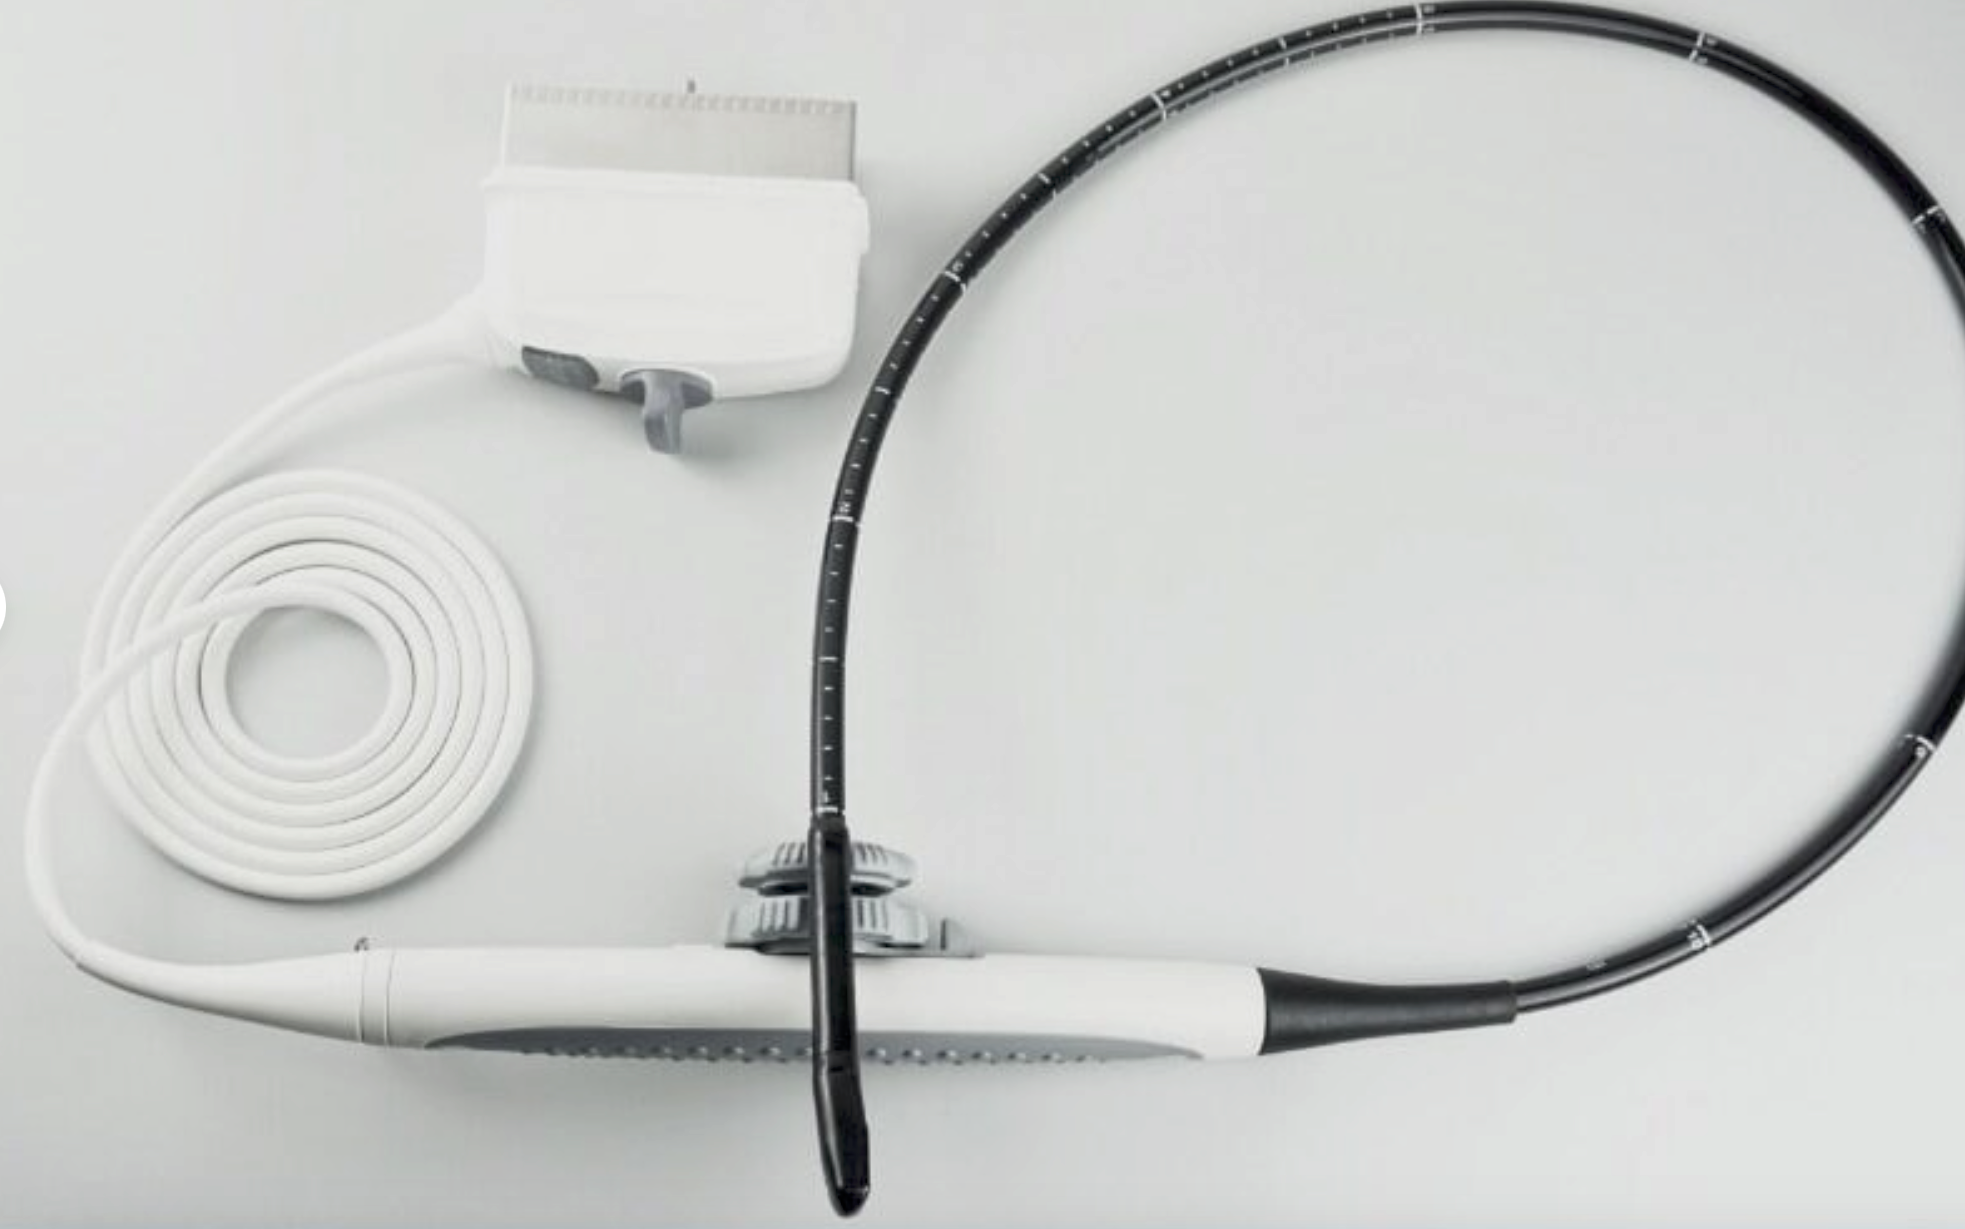

The CE Digital Laptop Ultrasound Scanner is designed to provide high-quality imaging for medical professionals. With its advanced 7.5MHz linear probe, this scanner captures clear and precise images, allowing for accurate diagnostics. It is especially beneficial for procedures requiring detailed visualization, such as vascular and musculoskeletal examinations. This tool empowers healthcare providers, so they can deliver better patient care through enhanced imaging technology.

This laptop ultrasound scanner is lightweight and compact, making it highly portable. Doctors can easily transport it between rooms or different facilities, ensuring they always have access to essential diagnostic tools. Furthermore, its user-friendly interface allows even those with limited ultrasound experience to operate it effectively. Therefore, healthcare professionals can quickly adapt and integrate it into their daily practices, maximizing efficiency.